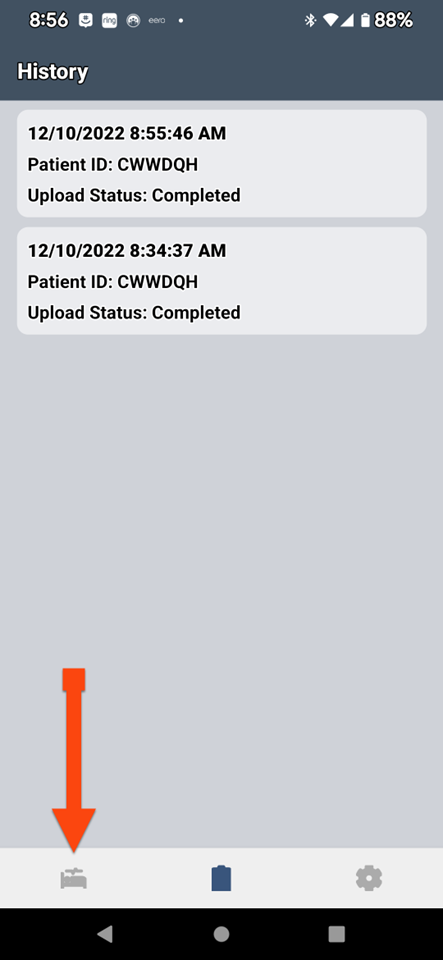

SLEEPIMAGE APP (Android)

SLEEPIMAGE APP (Android)

SLEEPIMAGE APP (Android)

SLEEPIMAGE APP (Android)

SLEEPIMAGE APP (Android)

SLEEPIMAGE APP (Android)

SLEEPIMAGE APP (Android)

SLEEPIMAGE APP (Android)

SLEEPIMAGE APP (Android)

SLEEPIMAGE APP (Android)

SLEEPIMAGE APP (Android)

SLEEPIMAGE APP (Android)

SLEEPIMAGE APP (Android)

SLEEPIMAGE APP (Android)

SLEEPIMAGE APP (Android)

SLEEPIMAGE APP (Android)

SLEEPIMAGE APP (Android)

SLEEPIMAGE APP (Android)

SLEEPIMAGE APP (iPhone)

SLEEPIMAGE APP (Android)

SLEEPIMAGE APP (Android)

SLEEPIMAGE APP (Android)

SLEEPIMAGE APP (Android)

SLEEPIMAGE APP (Android)

SLEEPIMAGE APP (Android)

SLEEPIMAGE APP (Android)

SLEEPIMAGE APP (Android)